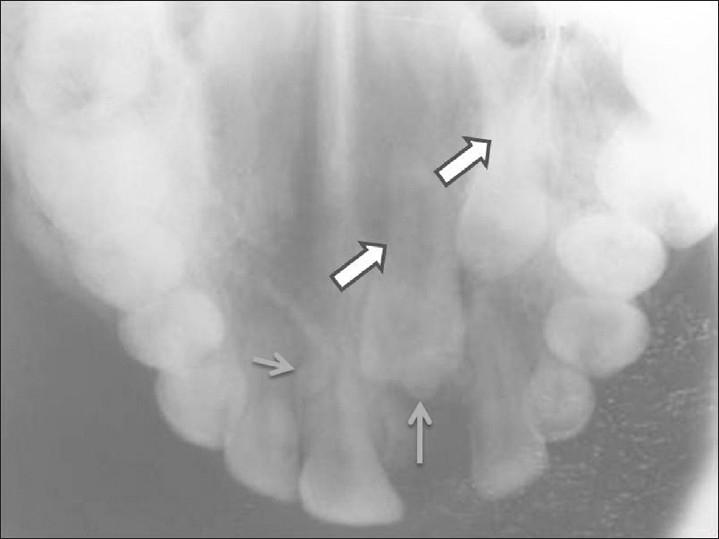

Gardner's syndrome is an autosomal dominant disease and is a subtype of familial adenomatous polyposis. It is characterized by adenomatous intestinal polyps, multiple osteomas in the skull, maxillae, mandible, and multiple cutaneous and subcutaneous masses (epidermoids and desmoid). Intestinal polyps, if not treated, have 100% chance of becoming malignant. We report a case of a 25-year-old female patient with Gardner's syndrome, with clinical manifestations including impacted supernumerary teeth, odontomes, sebaceous cyst on the scalp, and osteomas. It is important for the general dental practitioners to be aware of the clinical and radiological characteristics of Gardner's syndrome.

加德纳综合征是一种常染色体显性疾病,是家族性腺瘤性息肉病的一种亚型。其特征为肠道腺瘤性息肉、颅骨、上颌骨、下颌骨的多发性骨瘤以及多发性皮肤和皮下肿物(表皮样囊肿和硬纤维瘤)。肠道息肉若不治疗,恶变几率为100%。我们报告一例25岁加德纳综合征女性患者,临床表现包括阻生多生牙、牙瘤、头皮皮脂腺囊肿和骨瘤。普通牙科医生了解加德纳综合征的临床和放射学特征很重要。